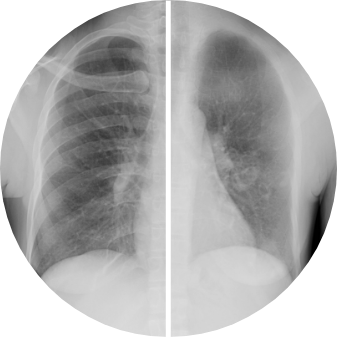

ClearRead CT with Clear Visual Intelligence provides an unimpaired view of the chest for efficient and accurate detection of cardiothoracic diseases. The full suite of tools detects, segments, and measures nodules, compares findings with prior exams, quantifies CAC, and automatically integrates with the radiology report. ClearRead CT is a natural addition for opportunistic CAC and nodule detection or as part of a lung cancer screening program. Detect 29% more nodules and read 36% faster.2,14